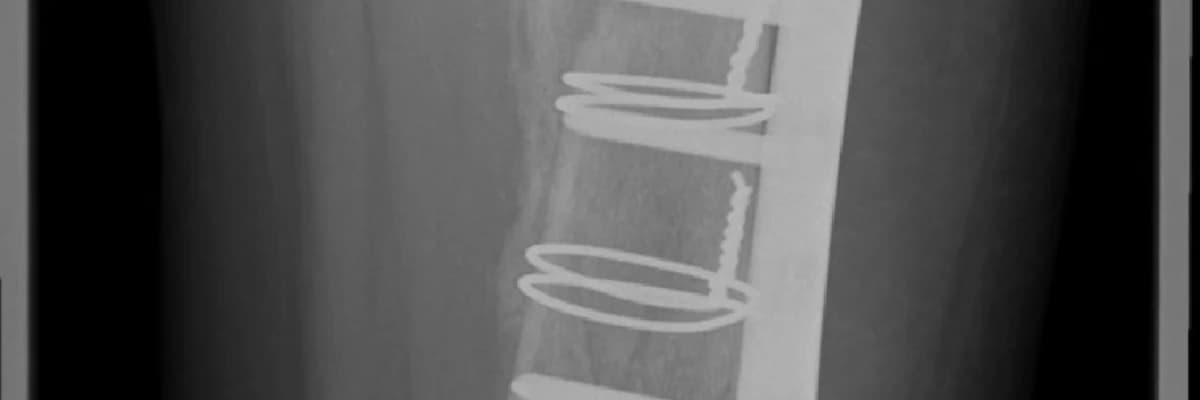

Birkaç hafta içinde başlayan bu evre, sihrin gerçekleştiği yerdir. Osteoblast adı verilen kemik yapıcı hücreler, yumuşak kallusu minerallerle (özellikle kalsiyum ve fosfor) besleyerek "sert kallus"a dönüştürür. Bu yeni kemik dokusu, röntgende artık kırık hattı etrafında bulutsu bir gölge olarak görülebilir. Ancak bu kemik hala kırığın orijinal gücüne sahip değildir; kırık hattı hala hissedilebilir.

Hızlandıranlar: Genç yaş, iyi beslenme (yeterli protein, Kalsiyum, D Vitamini, C Vitamini), sigara içmemek, kırığın uygun şekilde sabitlenmesi (alçı, platin vb.), düşük dereceli egzersizler (doktor kontrolünde).